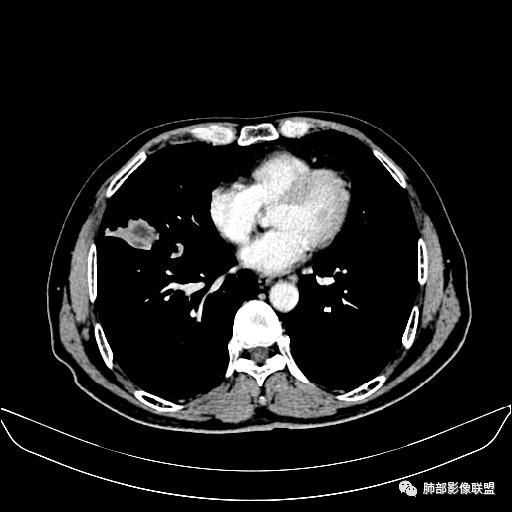

住院4天后行胸部增强CT

动脉期

右中叶团块状影不均匀强化伴坏死,中叶支气管及血管侵犯,考虑癌肉瘤>恶性神经内分泌肿瘤>腺鳞癌

主体病灶在中叶外侧段,病灶分叶膨隆,血管进入受侵犯,坏死边界不清,纵隔淋巴结肿大,支气管受压改变,考虑腺癌。

老年男性,因“咳嗽咳痰1月余。”入院。病程中咳嗽咳痰,咳黄白痰,间断咯少许鲜红色痰血。PPD阳性。胸CT:右肺中叶外侧段支气管管腔阻塞,大片实性病变,病灶边缘光滑,部分边缘膨隆,可见分叶,肺门及纵隔可见肿大淋巴结,并可见钙化。增强可见病灶明显强化,而且延迟强化明显,病灶内多发低密度区,内见血管影,血管变细、部分血管破坏。考虑恶性病变可能性大,鉴别慢性肉芽肿性病变。

胸CT:跨叶大肿块,主体在中叶,右中叶外侧段支气管阻塞,病灶部分边缘膨隆,可见分叶,部分边缘平直,肺门及纵隔可见肿大淋巴结。增强病灶不均匀强化,延迟强化明显,病灶内多发低密度区,内见血管飘浮,部分血管变细、模糊。考虑:恶性病变可能性大,大细胞?淋巴瘤?鉴别慢性肉芽肿性病变。

右肺中叶软组织肿块,外围向内生长,叶间胸膜向前内移位,肿块近肺门侧跨叶,中叶外侧段支气管截断,密度不均匀,双侧肺门及隆突下见肿大淋巴结,增强后呈中度不均质强化,肺动脉供血,多发坏死区,边界尚清,坏死区域内见结构,结合病史考虑恶性,鉴别诊断1结核,爬行征是沿支气管树分布,外宽,内窄,周围有卫星灶,内气管狭窄后扩张,此例沿叶间胸膜长轴分布,气管有截断,不典型。2炎性肉芽肿,符合的地方下方层面增强后延迟性轻度环形强化,不符临床无发热等急性感染病史,实验室指标不符,病灶周围渗出及慢性炎性改变有,不明显。